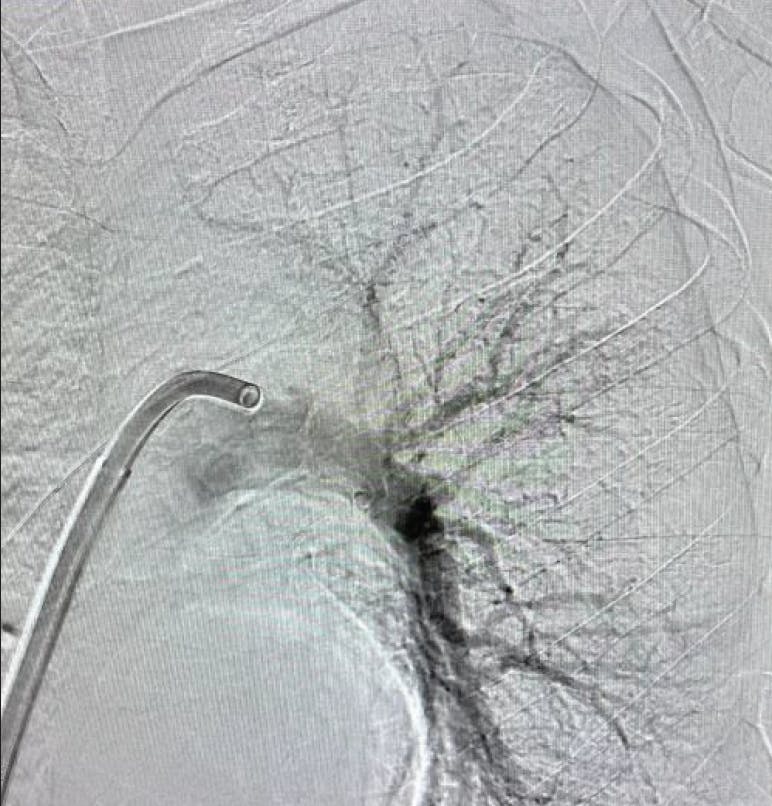

PATIENT PRESENTATION

A patient in his early 60s was admitted with bowel obstruction and colonic mass. The patient underwent resection 6 days prior and had an acute episode of shortness of breath and chest pain. Initial evaluation revealed a HR of 111 bpm, BP of 115/59 mm Hg, and oxygen saturation of 83%. Troponin I was 0.81 ng/mL and pro-BNP was 2,080 pg/mL. CTA revealed a large amount of thrombus concentrated within the right PA (Figure 1). There was evidence of right heart strain with an elevated RV/LV ratio of 1.35, and echocardiogram displayed right heart dysfunction.

Figure 1. Initial angiogram of right PA

Based on the patient’s lab results, they were placed at the intermediate-high-risk category for pulmonary thromboembolism and, subsequently, the decision was made to pursue CAVT with Lightning Flash.

INTERVENTION

Access was achieved in the right CFV. Initial diagnostic testing revealed a PA pressure of 53/28 mm Hg. The 16-F Lightning Flash device was advanced into the right PA, and the flow switch was turned on to deliver continuous aspiration to the thrombus (Figure 2). By the conclusion of the case, there was complete resolution of thrombus and an EBL of < 200 mL. Postprocedure PA pressure was 38/17 mm Hg (Figure 3 and Figure 4). The patient experienced immediate clinical improvement in oxygen saturation and HR as well as resolved shortness of breath following the intervention.

Figure 2. Preprocedural venogram.

Figure 3. Post-thrombectomy angiogram.

A patient in her early 40s with history of PE, severe obesity, hypertension, and iron deficiency presented to the ED with extreme shortness of breath. CT scan showed a saddle PE extending down the right PA in addition to several small distal thrombi; the thrombus extended to the PA bifurcation, almost completely occluding flow to the segmental arteries throughout the right lung (Figure 2).

Figure 1. Left lobe initial angiogram.

Figure 2. Right lobe initial angiogram.

On the left, there was thrombus in the proximal left pulmonary artery (Figure 1). Initial evaluation showed stable hemodynamics except for tachycardia, with a HR of 115 bpm, and revealed BP of 145/110 mm Hg, mild tachypnea, and 98% saturation on 2 L of oxygen. The patient had an RV/LV ratio of 1.4, indicating right heart strain. An echocardiogram showed mildly dilated right ventricle and mild systolic dysfunction, an estimated systolic pressure of 50 mm Hg.

Cardiac enzymes including troponin and proBNP were both elevated; in the setting of submassive PE, the decision was made to pursue aspiration thrombectomy with Lightning Flash, with the goal of preserving RV function and preventing the development of pulmonary hypertension. The challenging point was the presence of saddle PE, pulmonary hypertension, and severe obesity.

Access was obtained in the right groin, and an angiogram was performed to confirm the patency of the inferior vena cava and the iliac veins. Over the wire, a 16-F, 33-cm Gore DrySeal sheath was placed, and a Swan-Ganz PA catheter was advanced to the PA to measure the hemodynamics and measure the cardiac output. After exchanging for the 16-F Lightning Flash aspiration catheter in the right lung, aspiration thrombectomy was initiated (Figure 3).

Figure 3. Intraprocedural angiogram.

Upon confirming vessel patency and thrombus removal with an angiogram (Figure 4, Figure 5, and Figure 6), right heart catheterization from the side port was performed, showing a significant drop in PA pressure from systolic 67 down to 49 mm Hg and excellent hemostasis. By the conclusion of the case, the patient no longer required supplemental oxygen, had no chest pain or shortness of breath, and experienced no significant bleeding. The patient was cleared for discharge the next day.

Figure 4. Post-thrombectomy right lobe angiogram.

Figure 5. Post-thrombectomy left lobe angiogram.